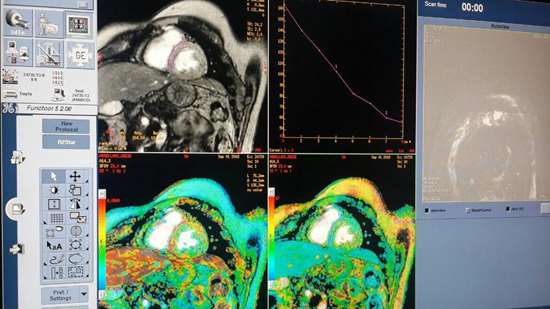

راه اندازي تكنيك تصويربرداري MRI T2 star در زاهدان

برای اولین بار تكنيك تصويربرداري MRI T2 star در مرکز mri بیمارستان علی ابن ابی طالب (ع) زاهدان راه اندازی شد

راه اندازي تكنيك تصويربرداري MRI T2 star در زاهدان

برای اولین بار تكنيك تصويربرداري MRI T2 star در مرکز mri بیمارستان علی ابن ابی طالب (ع) زاهدان راه اندازی شد

دكتر ميري علی آباد معاون درمان دانشگاه با اعلام این خبر افزود : این تکنیک تصویربرداری جهت اندازه گيري میزان رسوب آهن در قلب و کبد بیماران تالاسمی ماژور کاربرد دارد و مرکز MRI بيمارستان علي ابن ابيطالب(ع) زاهدان برای اولین بار در استان این پروتکل را اجرا نموده است.

وی ادامه داد: از مهم ترین عوارض تالاسمی ماژور و اینترمدیا، رسوب آهن در بافت ها و ارگان های بدن از جمله قلب، كبد، پانكراس، غدد تيروييد، پاراتيروييد و غيره می باشد که سبب اختلال در عملکرد اين ارگان ها می شود.

به گفته دکتر میری علی اباد؛ یکی از روش های ارزیابی ميزان ذخيره آهن در بافت، بیوپسی است اما تهاجمی بودن این روش و عدم پذيرش بيماران، باعث شده تا از روش غیرتهاجمی تصویربرداری با T2* MRI

به عنوان روش جايگزين و دقيق جهت اين هدف استفاده شود.

وي تصريح كرد : همه بيماران تالاسمي ماژور بالاي ٨ سال بايد ساليانه تحت تصويربرداري با اين تكنيك قرار گيرند كه تاکنون بيماران بايد به ساير استان ها از جمله تهران، خراسان رضوي و فارس مراجعه ميكردند كه با راه اندازي اين تكنيك تصوير برداري در بيمارستان علي ابن ابيطالب(ع) زاهدان نيازي به مراجعه بيماران به ساير استان ها نميباشد.